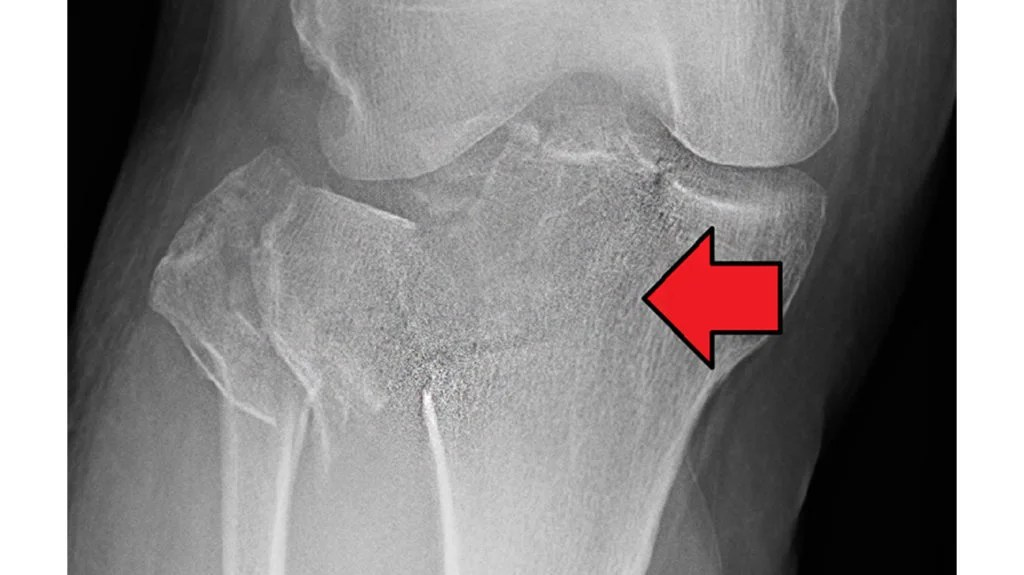

How is a Tibia Fracture Diagnosed?

Diagnosis involves clinical assessment and imaging. A healthcare professional may:

- Review how the injury occurred and assess symptoms

- Examine the leg for tenderness, swelling, and alignment

- Request imaging such as X-rays

- Use CT scans or MRI where further detail is required

Accurate diagnosis helps guide appropriate management.